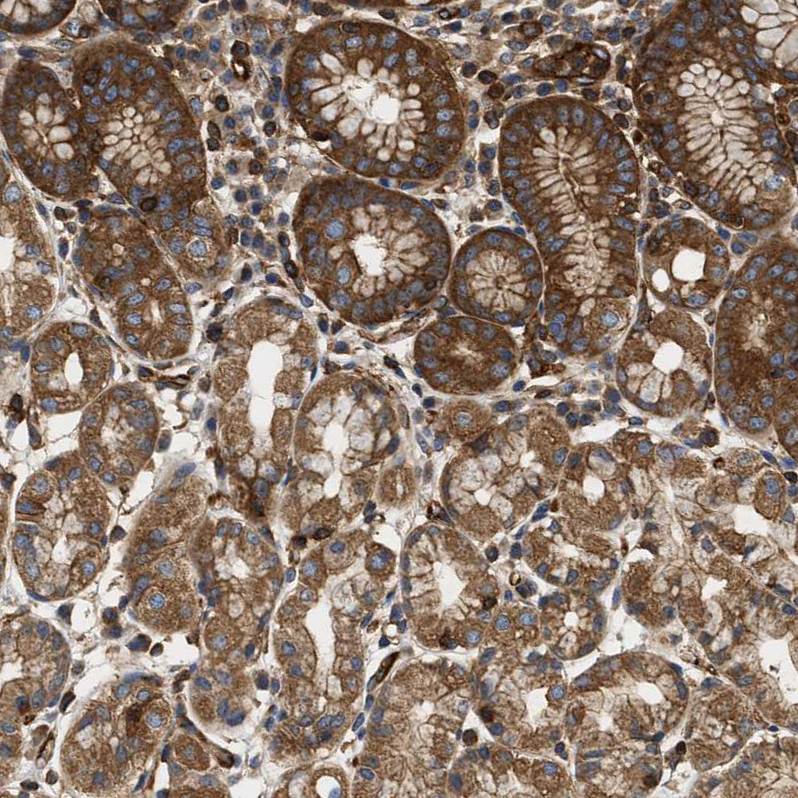

Immunohistochemical staining of human lymph node, placenta, stomach and testis using Anti-SAMD9L antibody HPA019461 (A) shows similar protein distribution across tissues to independent antibody HPA019465 (B).